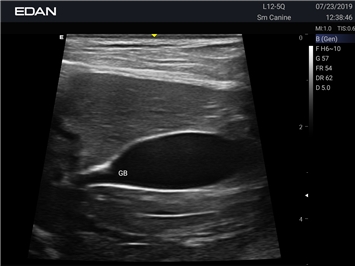

EDAN Acclarix AX2 VET

Ветеринарный ультразвук одним нажатием. Система Acclarix AX2 VET разработана с целью обеспечить бескомпромиссную производительность по доступной цене. Наличие уникальных двойных аккумуляторов в легком корпусе массой 4,5 кг из магниевого сплава позволяет системе Acclarix AX2 VET удовлетворять все потребности ветеринарных исследований, сохранив низкую стоимость.

EDAN Acclarix AX2 VET представляет собой специализированную ветеринарную ультразвуковую систему, сочетающую высокую производительность с доступной ценой. Благодаря продуманной конструкции и передовым технологиям, система обеспечивает качественную диагностику животных различных видов.

B-режим, Двухмерное сканирование:

Да